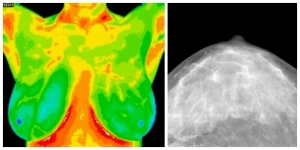

thermography-vs.-mammogram